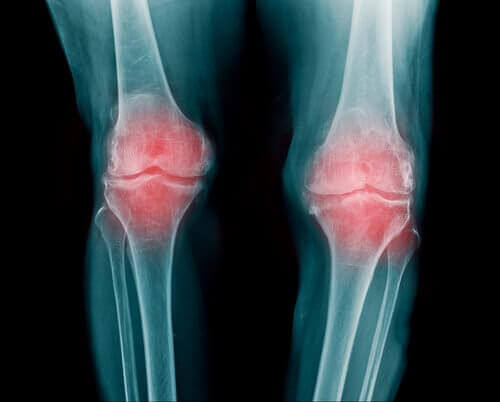

Eklemleriniz vücudunuzdaki kemiklerin uç kısımlarında bulunur. Bu eklemler kondillerinizi koruma görevine sahiptir. Ayrıca alt ve üst uzuvlarınızın hareketinde önemli bir role sahiptir. Bu yazımızda osteoartriti önlemek için 5 muhteşem yiyecekten bahsediyoruz.

Eklemleri fazla zorlamak birçok çeşit hastalığa sebep olabilir. Bunların arasında osteoartrit en başta gelir.

Her eklemin arasında kıkırdak bir kısım vardır. Bu da kemiklerinizin birbirine sürtünmesini engeller. Ancak zamanla bu kıkırdakta kademeli olarak azalmalar görülür. Bunun sonucunda da ağrı ve enflamasyon baş gösterir.

Sonuç olarak, hareketleriniz önemli ölçüde kısıtlanır. Bununla beraber çeşitli aktiviteler yapma özgürlüğünüz azalır.